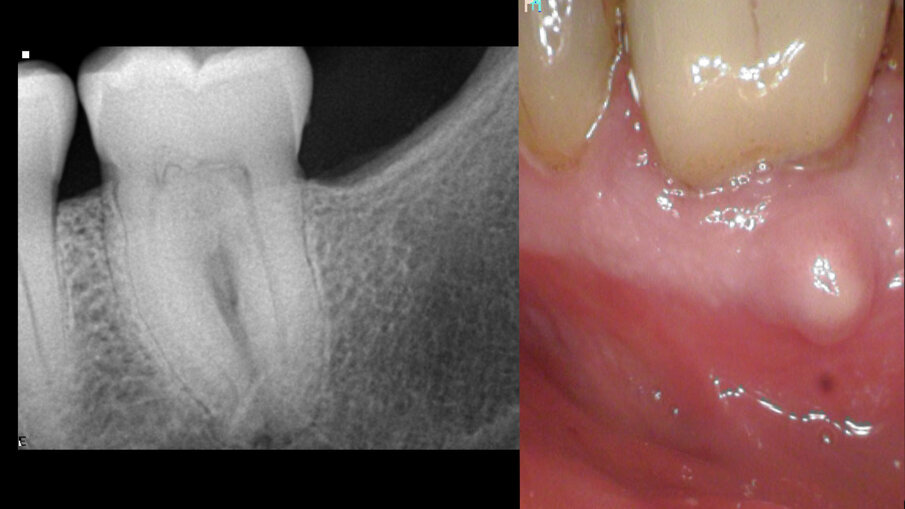

Ovaj pacijent je hitno došao zbog oštrog bola u drugom maksilarnom molaru. Ovo je potvrđeno kliničkim pregledom. Napravljen je standardni radiograf (Sl. 1), koji pokazuje veoma složenu anatomiju i kalcifikovanu pulpnu komoru. Istorija ovog zuba, kako je opisao pacijent, bila je da je na njega postavljen inlej i nakon nekog vremena se pojavila nelagodnost koja je trajala nekoliko godina bez lečenja. Na pregledu mu je rečeno da je sve u redu.

Sl. 1: Rendgen snimak pre operacije, koji pokazuje veoma složen sistem korenskih kanala i kalcifikovanu pulpnu komoru